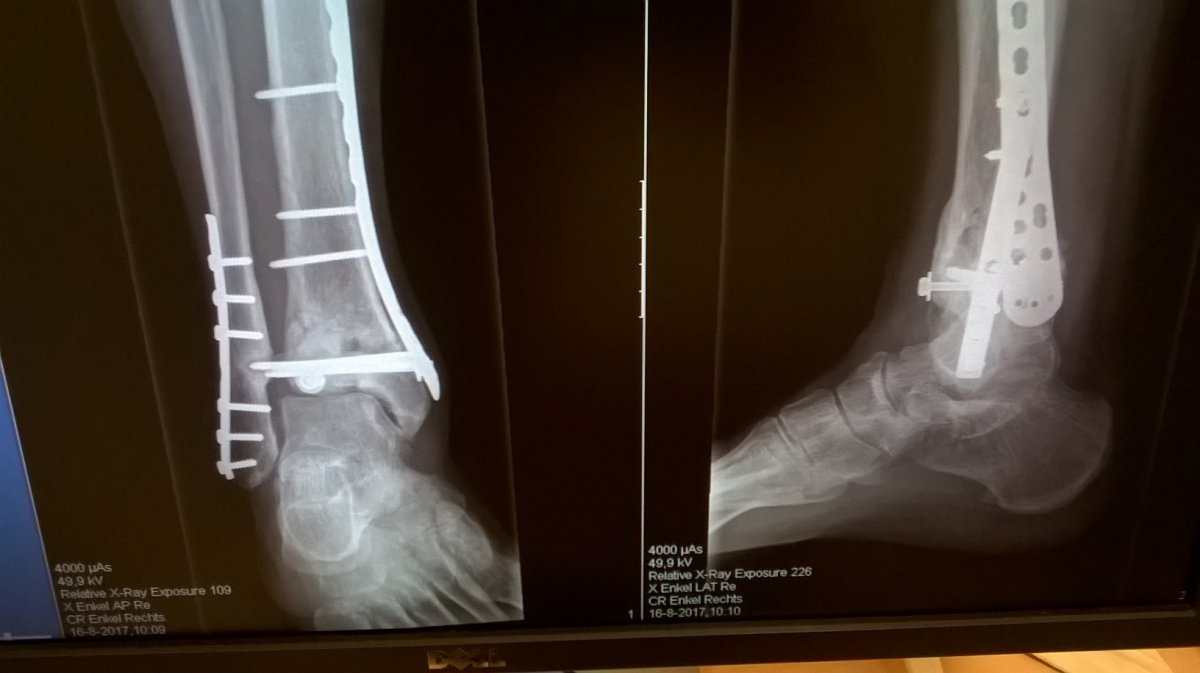

Maar de arts ziet kennelijk wel verschil neem ik aan?Eerlijk gezegd zie ik niet veel verschil lees vooruitgang met de foto's van 28 maart jongstleden